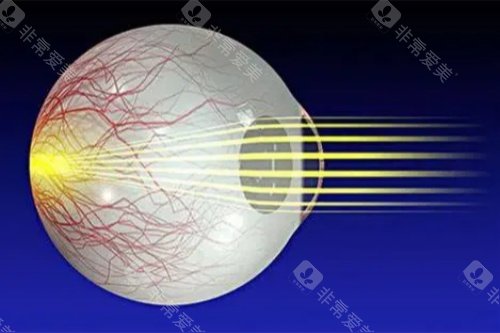

视网膜脱落的治疗方法有多种。对于尚未发生脱离的视网膜裂孔,可采用激光治疗,利用激光封闭裂孔,防止视网膜脱落。传统的巩膜环扎术和巩膜外加压术,适用于单纯的早期视网膜脱离。